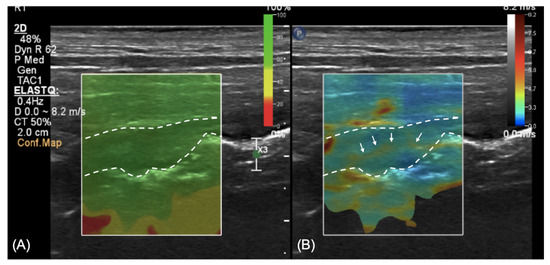

2.2. Imaging Diagnosis